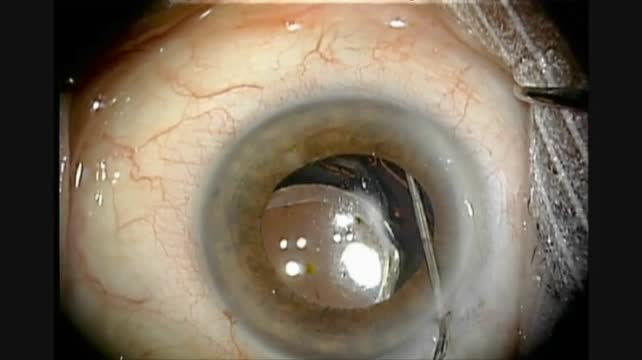

Morgagnian Cataract

Jocelyn S. Kasanardjo, MD, and Gelre Ziekenhuizen Apeldoorn, MD